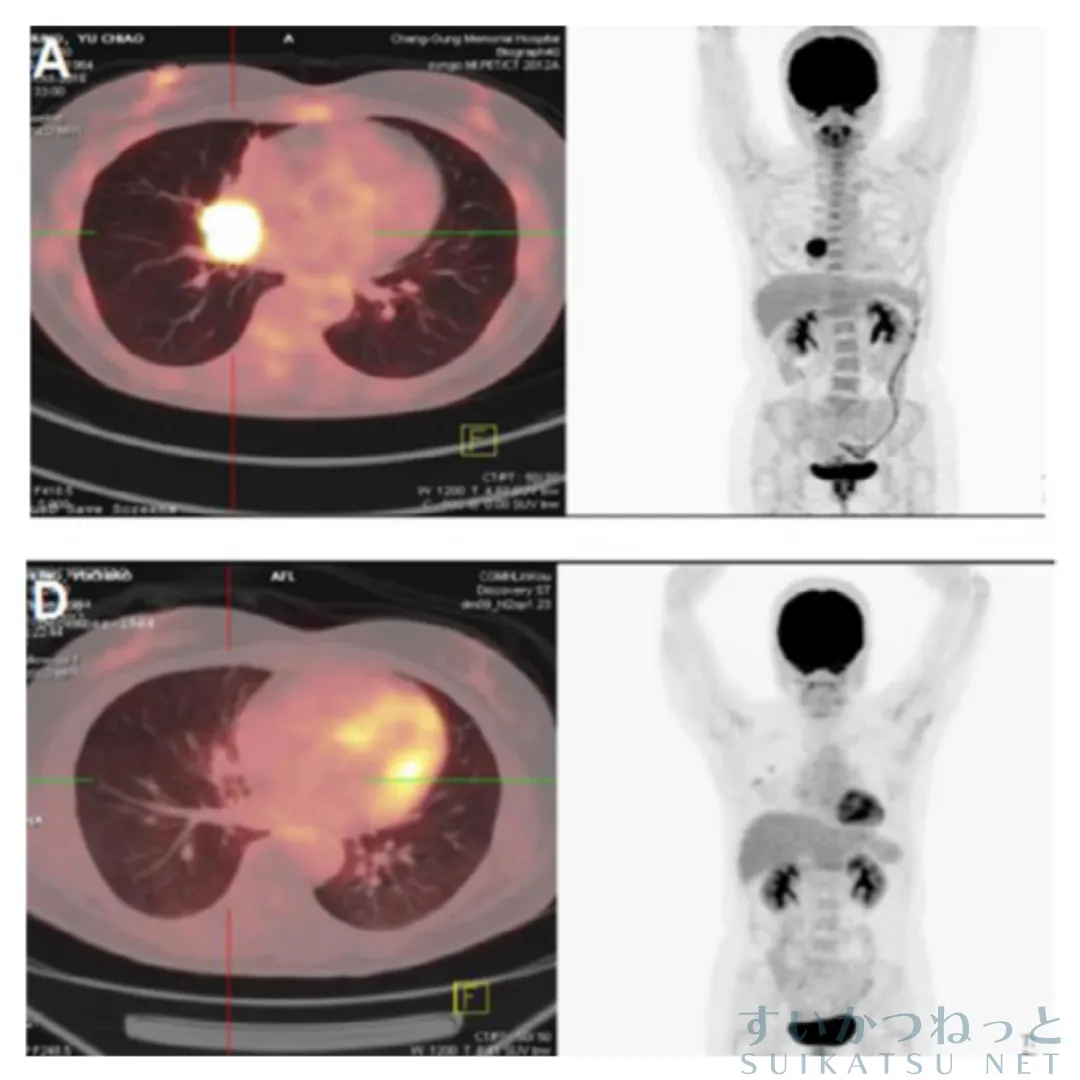

がん種別では肺がんで75%と最も高く、膵臓がん・肝臓がんでは低下例がなかった。 以下は、肺がんが消失した患者の1例。

全体の病勢制御率は57.5%で、ステージIIIの患者では84%と高い制御率が得られた(p=0.0167)。完全消失や部分縮小が確認され始めたのは開始から21〜80日目(中央値55日)であった。